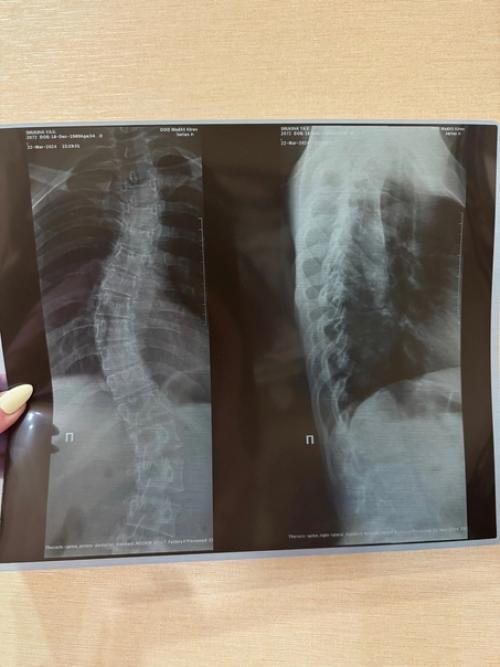

Я в этой теме давно, так как у меня врожденная дисплазия соединительной ткани, мой позвоночник возрастом как у подростка, хоть мне 34 года.

Дело в том, что искривление связано с нижестоящими регионами ( таз, колено, стопа, хотя и верхние влияют на формирование осанки).

Главное знайте - до 2 степени сколиоза - упражнения из кинезитерапии помогают, после 2 степени результатов не увидите.

Внимание! Только в том случае, если по градусам дуги, уже больше чем 2 степень - тогда инструктор медицинского фитнеса, владеющий минимум сертификатами шрот - терапии и Seas, а так же наличие медицинской лицензии в центре, где такая работа с вами осуществляется.